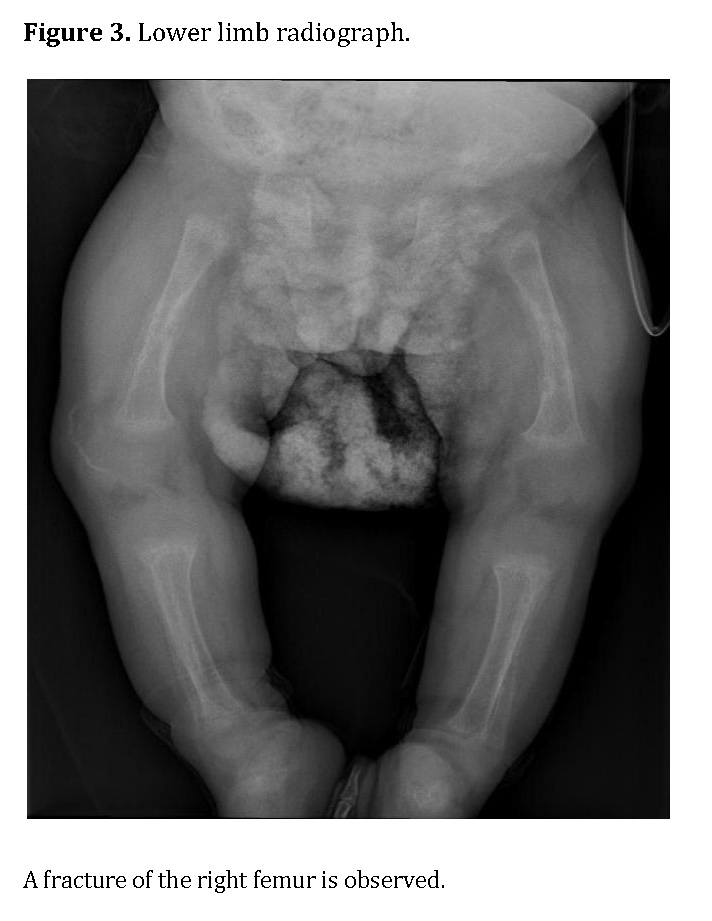

Chest radiography showed bilateral heterogeneous parenchymal infiltrates, pleural thickening, and right-sided rib fractures in the consolidation phase (Figure 1). Radiographs of long bones revealed severe osteopenia, periosteal reaction, and multiple pathological fractures, including the right and left humerus, right ulna, and right femur (Figures 2 and 3).

Figure 3.